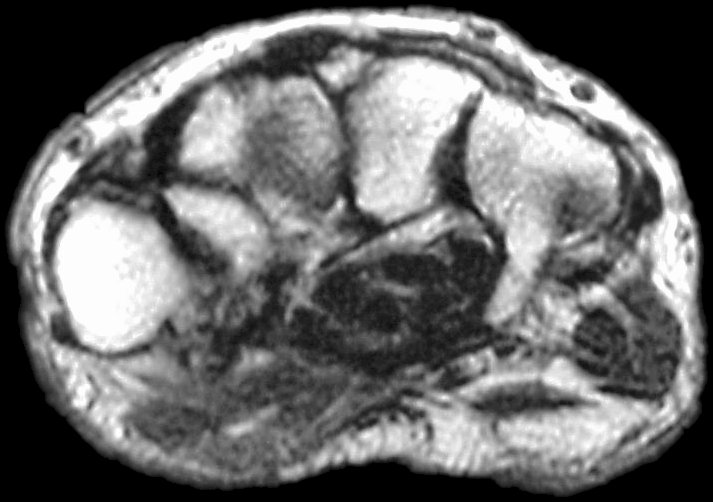

Sections through the carpal tunnel -  looking for a hook of hamate fracture or tendon discontinuity - were read as normal, although there may be a subtle signal irregularity through the hook of the hamate:

Is that a tendon rupture adjacent to the pisotriquetral joint?